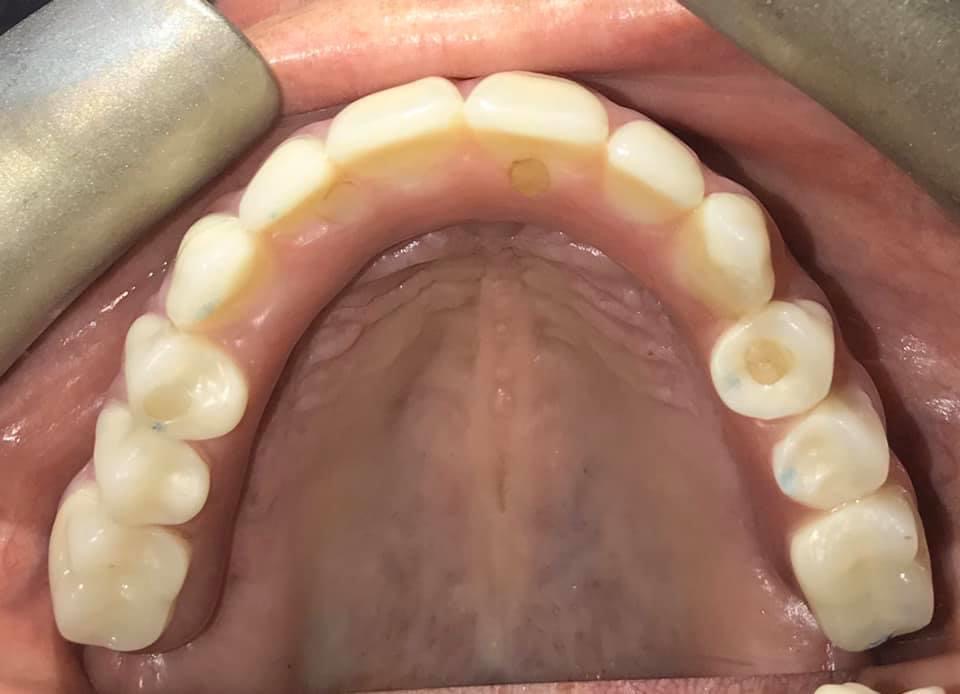

All- On- 5 technique: Implant Retained Dentures that patient does not remove